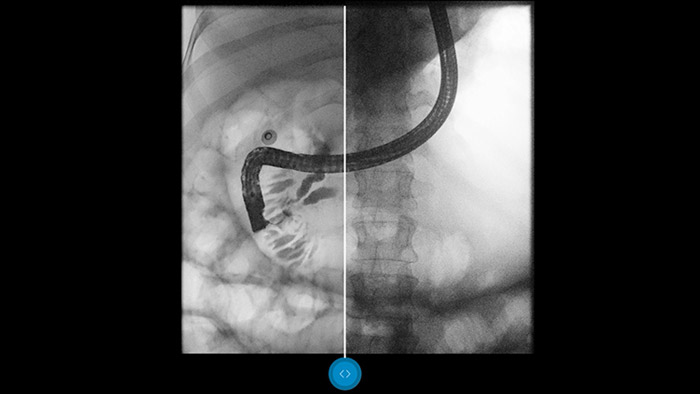

Descubra cómo funciona Dynamic UNIQUE

Compárelo con un procesador de imágenes convencional para ver los beneficios usted mismo.